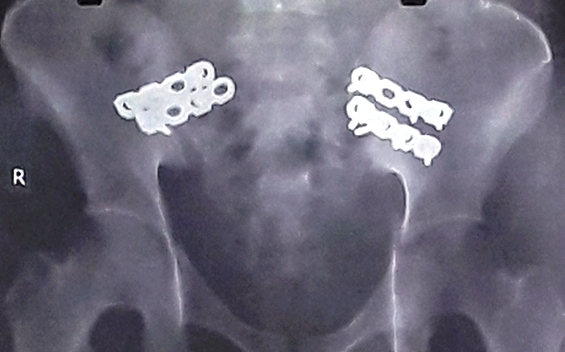

Khung chậu bệnh nhân được cố định qua ảnh chụp X-quang

Sau khi xong thì ngay lập tức các bác sĩ của Bệnh viện chấn thương chỉnh hình thực hiện cố định khung xương chậu bị gãy, kiểm soát sốc cho bệnh nhân. Trải qua 3 tiếng phẫu thuật, BS đã truyền 4 lít máu vào người bệnh, nạn nhân bắt đầu ổn định, da hồng hào trở lại, chỉ số huyết áp cân bằng. Đội ngũ Y bác sĩ thở phào nhẹ nhõm.